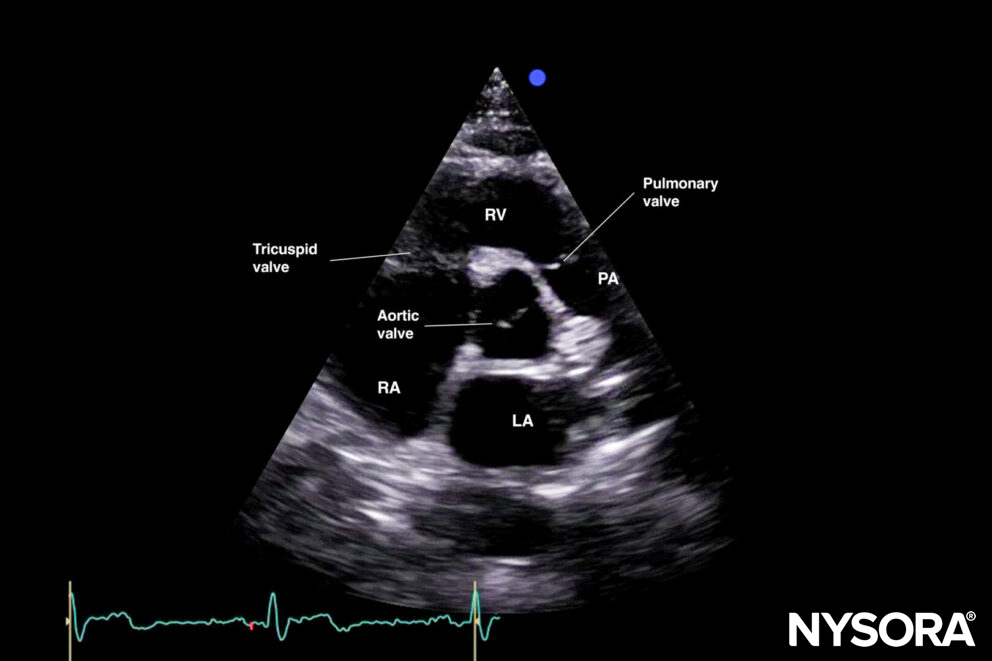

A. Aortic valve level: ‘Mercedes Benz’ view: This is a good view to assess the aortic valve, the right ventricle, the tricuspid valve, and the pulmonary valve.

Tilting or sliding in the parasternal short-axis position provides 4 images: A. Aortic valve level (Mercedes-Benz view), B. Mitral valve level (fish mouth view), C. Papillary muscle level, D. Apical level.